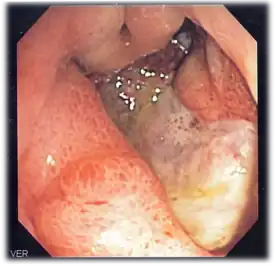

Endoscopic image of a posterior wall duodenal ulcer with a clean base, which is a common cause of upper GI hemorrhage.